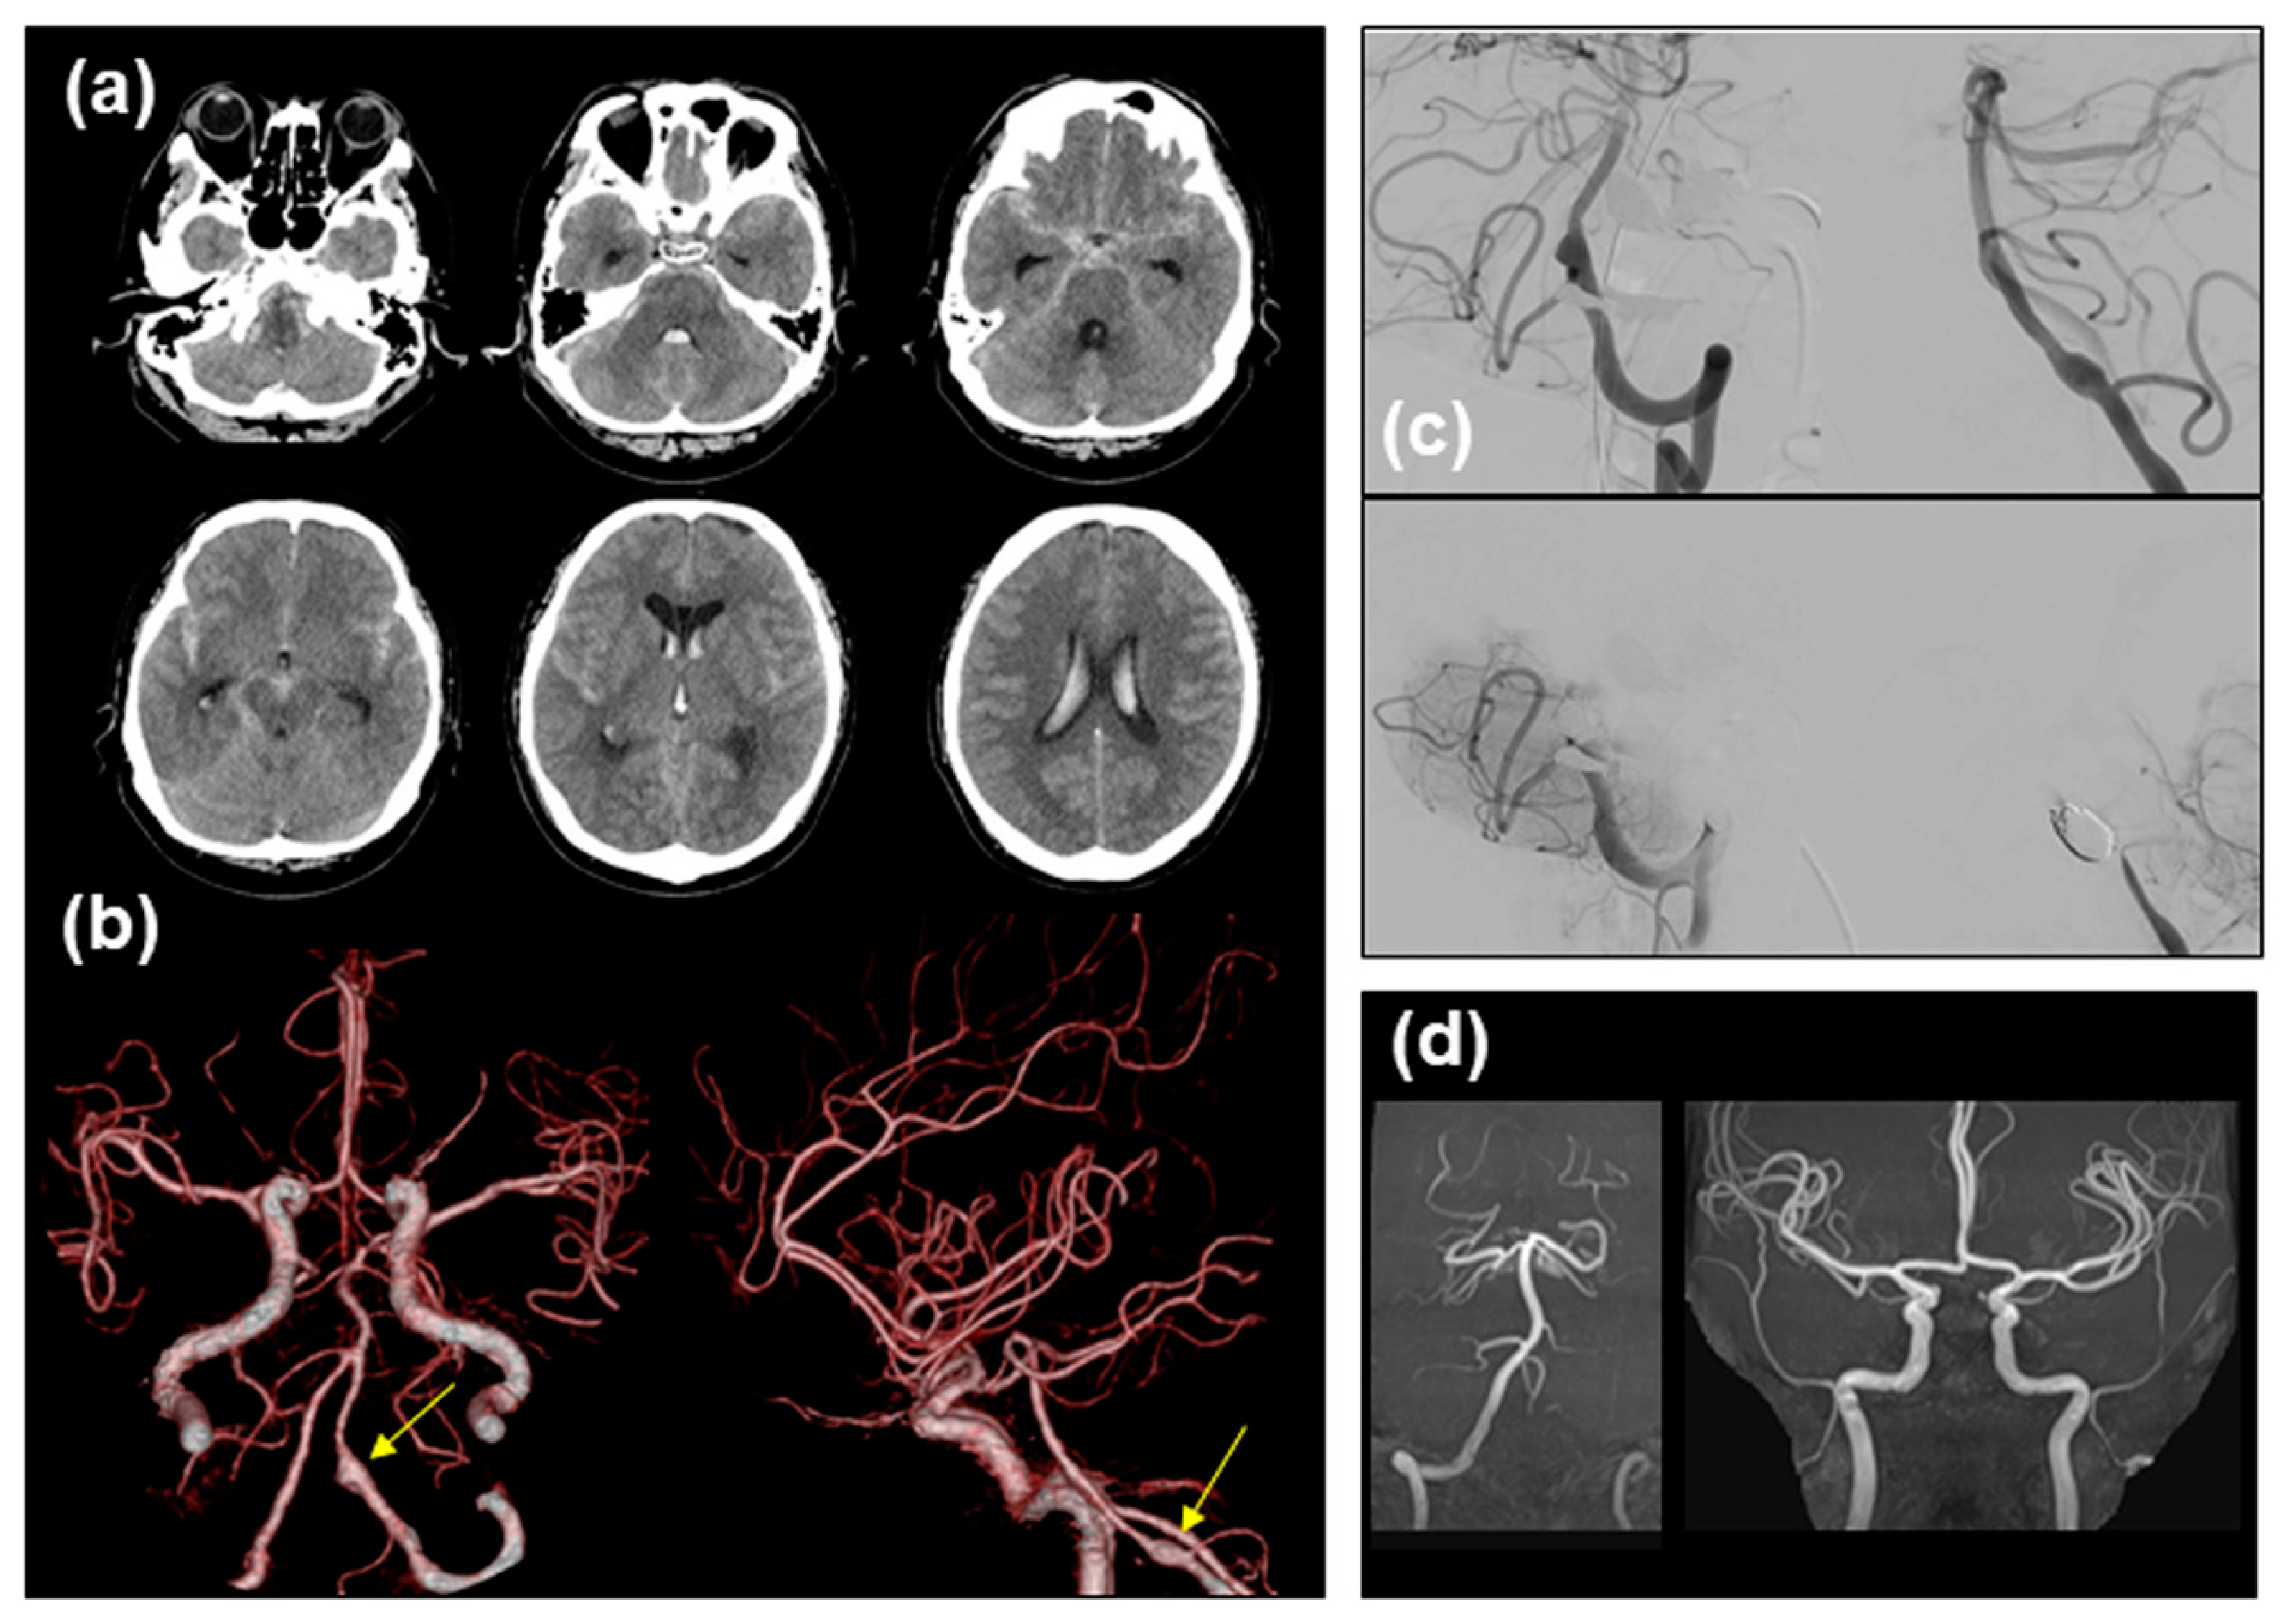

2. Case Report

2.1. Case Presentation

2.2. Contracting Case without Vasospasm